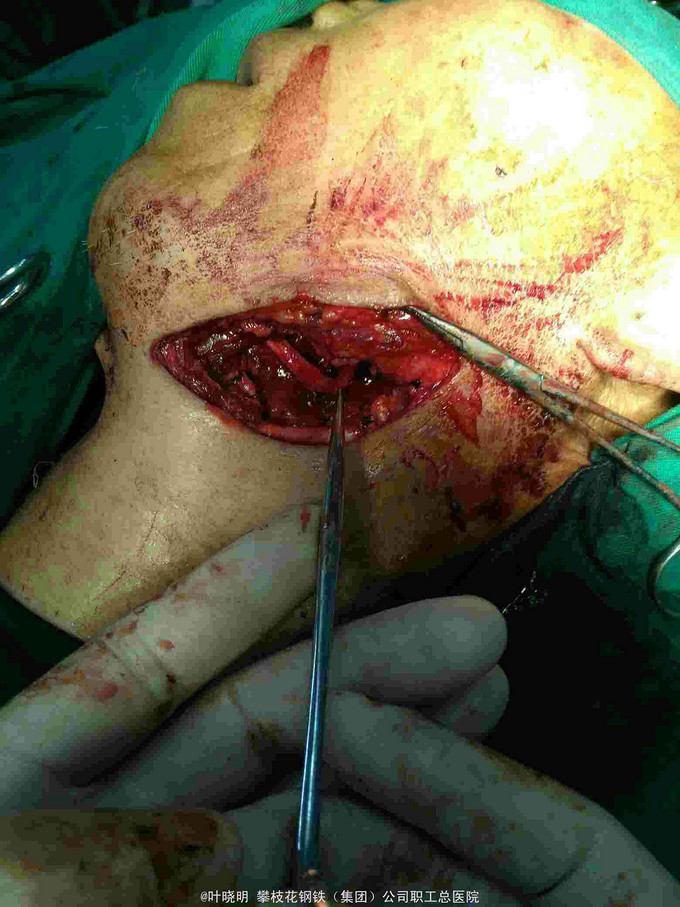

诊断:左颌下巨大包块待诊 1:左颌下腺腺瘤 2:腺瘤恶变? 治疗:2016.03.15上午全麻下常规左颌下切口,切开皮肤、皮下、颈阔肌妥善保护好左面N下颌缘支;拮扎面前Ⅴ和颌外A远心端,摘除面淋巴结,显露二腹肌前、后腹及中间键;见包块与颌下腺融合为一体,抽除出咖啡色内容物约10ml让包块体积缩小使于解剖分离。从前向后纯分离,见舌N袢被挤向浅面,妥善分离并保护之。在二腹肌前腹深面寻找颌下腺导管并近口腔侧拮扎;在二腹肌后腹深面寻找颌外A近心端并双重拮扎之;此时标本已完全游离,完整摘除并送冰冻。 稍后冰冻报告结果为‘’多形性腺瘤‘’。